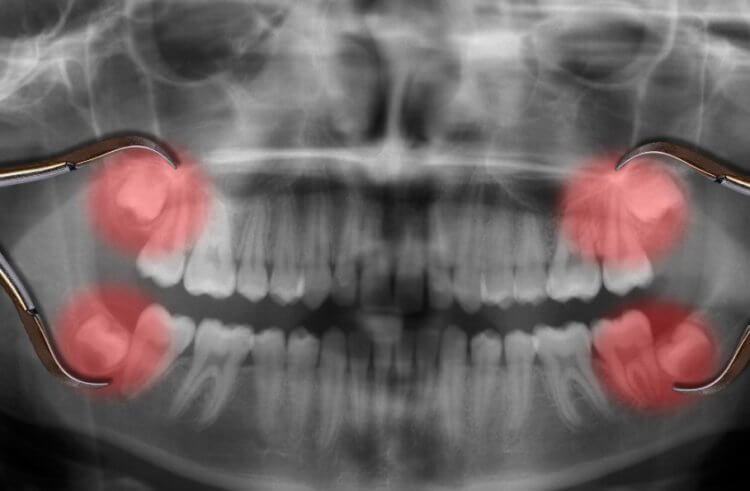

Считается, что полный набор зубов мудрости имеется у 92% населения Земли. У большей части остальных людей они не прорезаются из-за отсутствия места в зубном ряду. Но есть и люди, у которых за всю жизнь не появляется ни один третий моляр — их организмы на это попросту не запрограммированы. Например, в число таких счастливчиков входят коренные народы Мексики, которые даже не подозревают о существовании дополнительных зубов. Считается, что отсутствие третьих моляров заложено в них на генетическом уровне.

Зубы мудрости на рентгеновском снимке

В 2014 году ученые даже собрали статистику по наличию и отсутствию коренных зубов. Так, 10-25% американцев с европейскими корнями не имеют хотя бы одного коренного зуба, то есть у них нет полного набора. У африканцев неполный набор коренных звуков встречается у 11% населения, а у азиатов — у 40% людей. У эскимосов, которые проживают в арктических регионах Канады, Гренландии и Аляски, полный набор третьих моляров тоже прорезается редко. А вот у жителей Тасманских островов коренные зубы вырастают почти всегда. Судя по всему, это связано с их рационом питания, который богат твердой пищей.